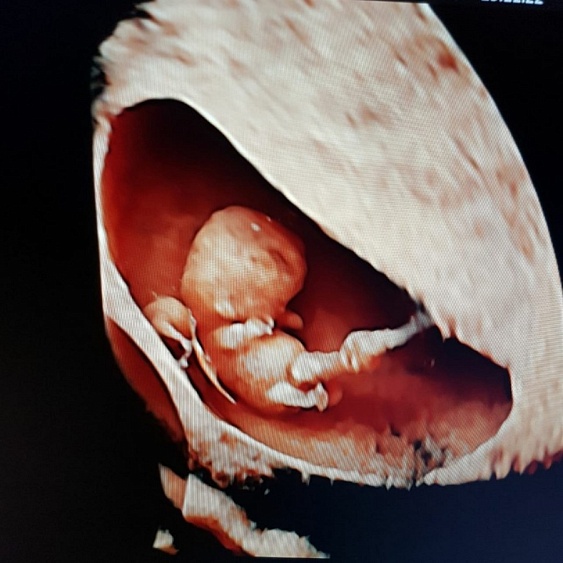

Женский центр «Мать и дитя» Кунцево с 16 по 30 апреля приглашает Вас провести экспертное УЗи плода и получить в подарок первую цветную фотографию вашего малыша.